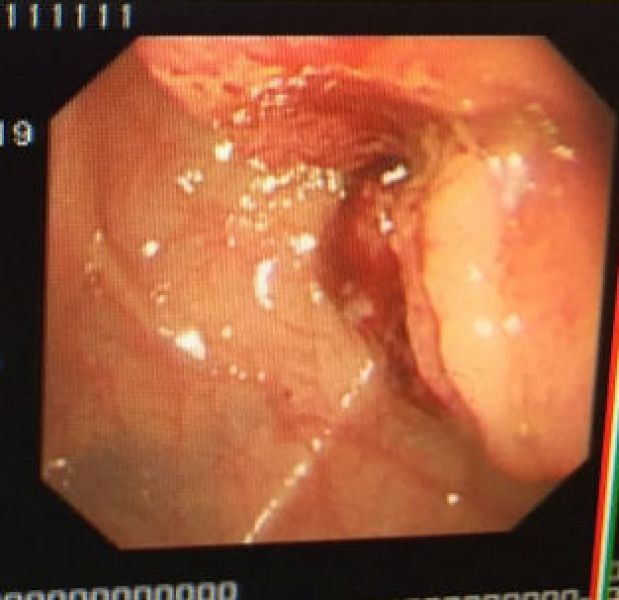

85岁张大爷,因腹痛、呕吐、肛门停止排便10余天拟肠梗阻收住消化一科,腹部CT提示升结肠癌并梗阻,肠镜见升结肠肿物,活检为中分化腺癌。患者高龄,一般情况差,不能耐受外科手术,大活人真要让屎憋死吗?消化内科、普外科讨论后于4月25日在介入室成功置入肠道支架,支架置入后,患者排气排便恢复,呕吐症状缓解,已进食半流质。

肠镜见升结肠肿瘤 造影见升结肠狭窄